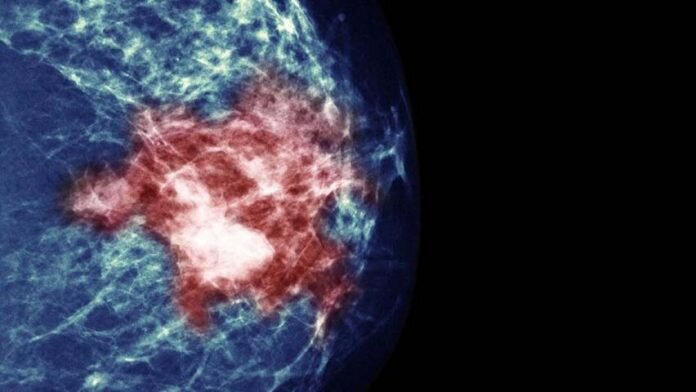

Эти продукты уменьшают риск рака молочной железы!